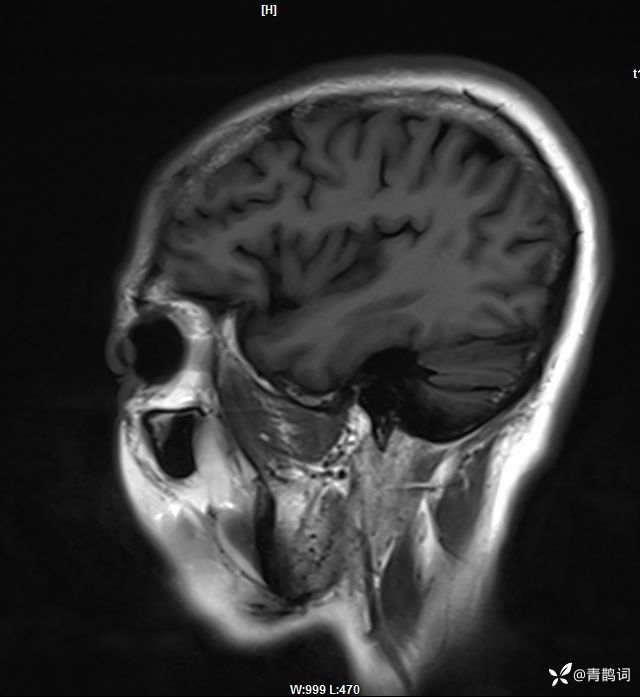

病例分享 | 45岁女患,7年的病史,结合影像学,如何诊断?

1、患者:女, 年龄:45岁

2、主诉:走路不稳渐加重7年,饮水呛咳伴头晕2年渐加重。

3、简要病史:患者于入院前7年出现走路不稳,表现为行走右偏,逐渐加重,易跌倒、不能自理;近2年出现饮水呛咳、吞咽困难及头晕;病程伴有耳鸣、反应迟钝,无恶心、呕吐。既往否认高血压、否认糖尿病、否认冠心病。

4、体格检查:体温36.0℃,脉搏80次/分,呼吸20次/分,血压140/70mmHg。查体:神清,构音障碍;眼球运动自如,双水平性眼震,左视时明显;双侧瞳孔等大同圆,左:右=3mm:3mm,对光反射灵敏;双侧额纹对称,双侧鼻唇沟对称;伸舌居中;四肢肌力4级,肌张力减低,四肢腱反射亢进,双侧Babinski征阳性;粗测感觉未见明显异常;四肢共济运动完成差,左侧为著;脑膜刺激征阴性。

入院后完善磁共振:

T2: